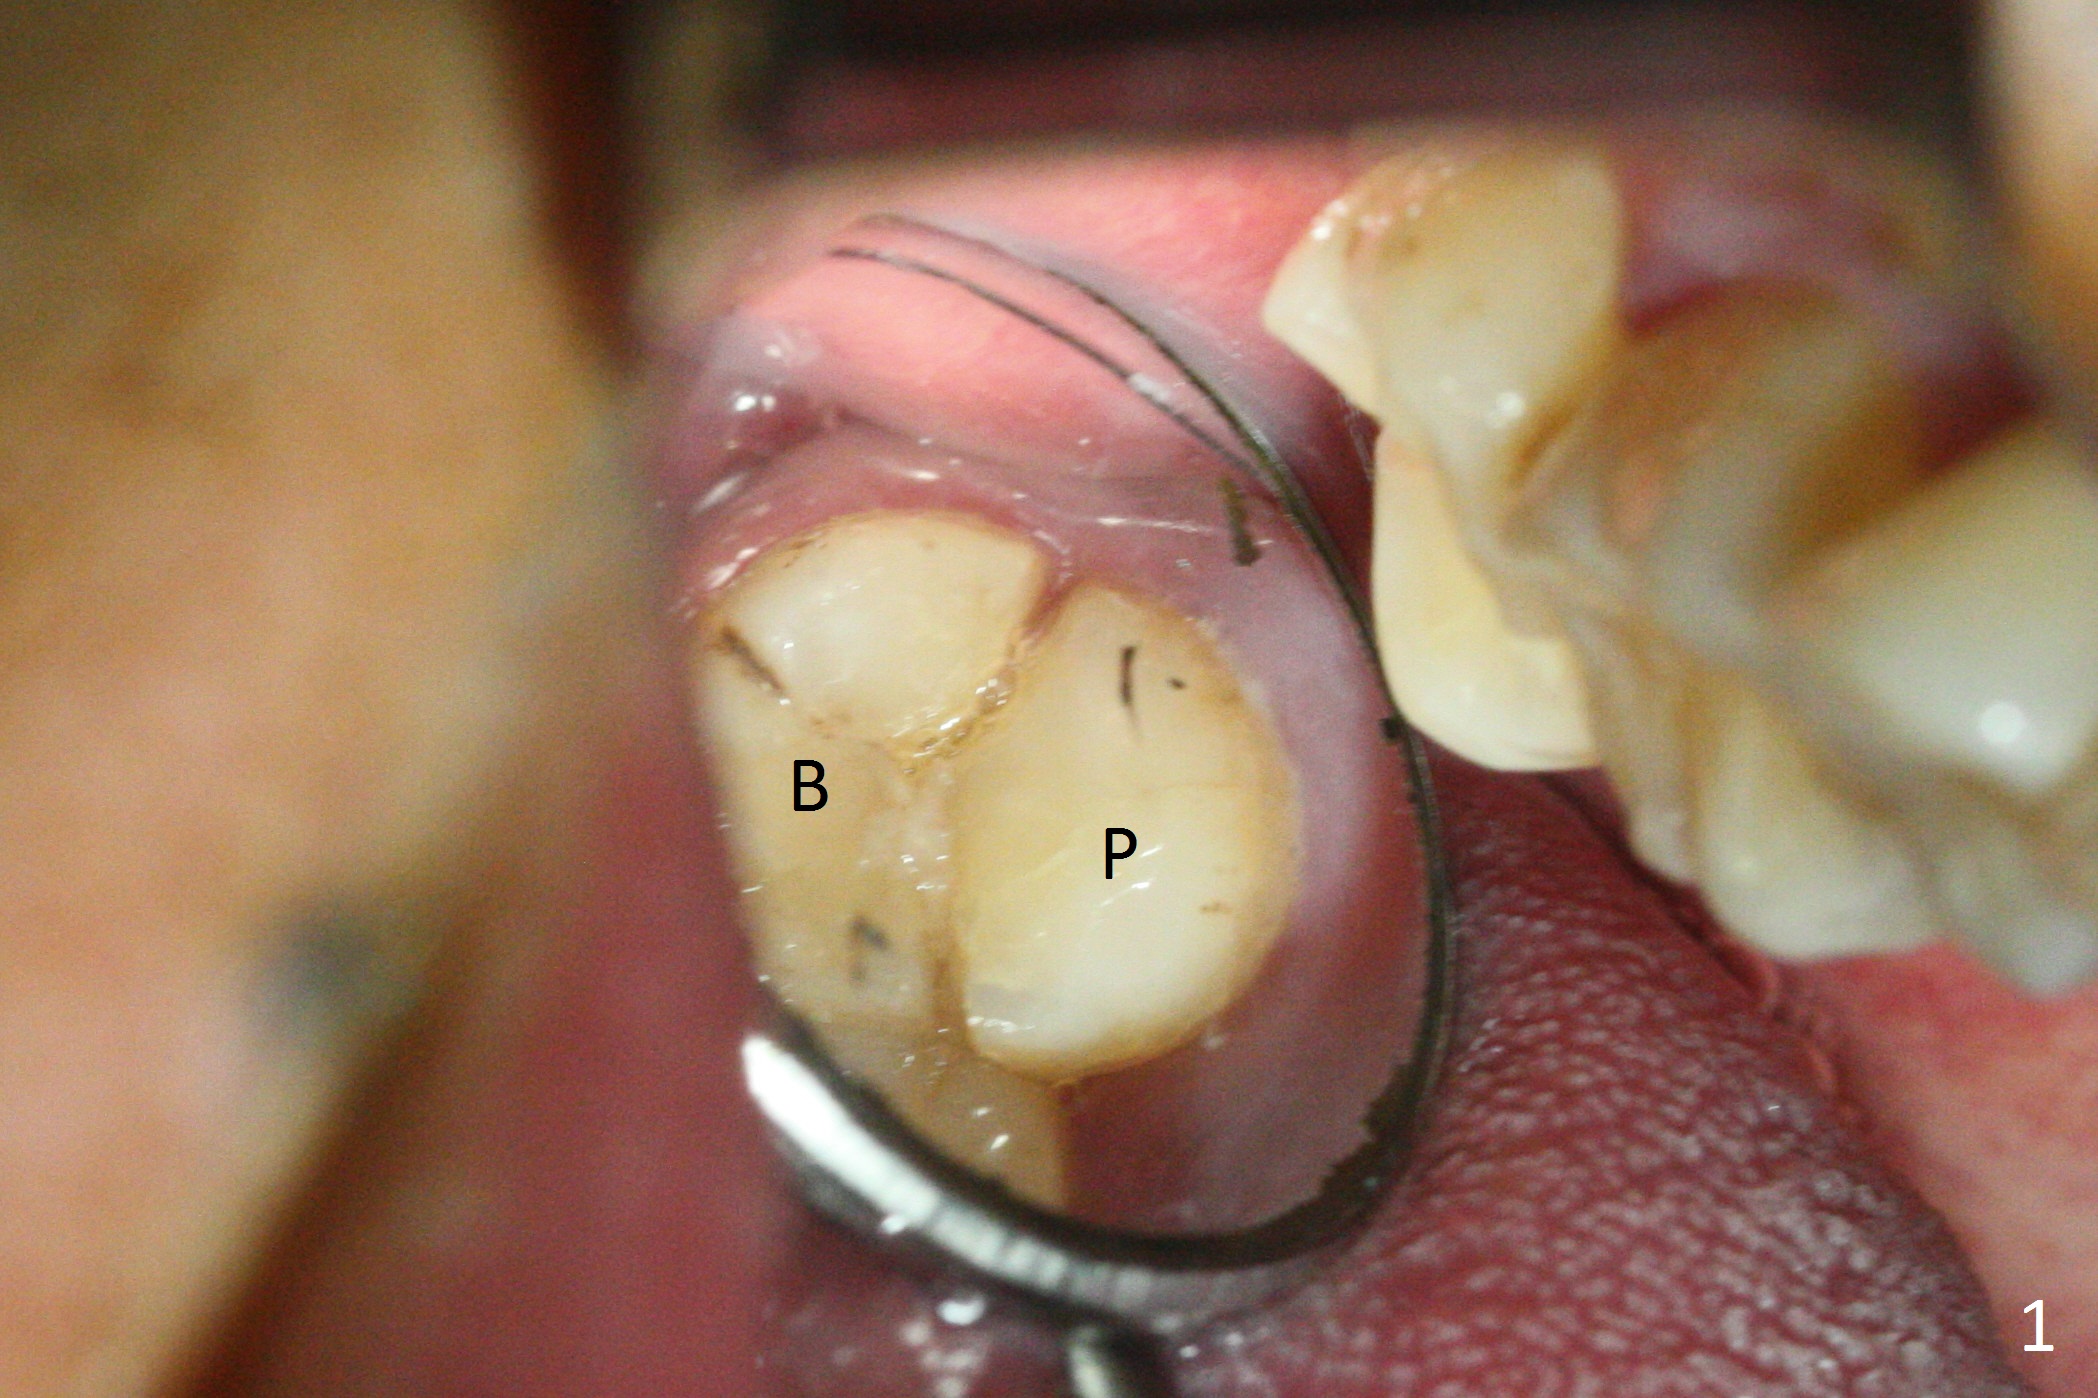

Preop exam shows that the tooth #2 has split into the buccal (Fig.1 B) and palatal (P) halves. When the tooth is extracted (Fig.2), there is a large piece of granulation tissue between these halves. The socket is large with sinus floor having pointed perforation. The latter is enlarged with rounded tapered Tatum osteotomy 2-4 mm, followed by tapered and then rounded taps. A 6.8x14 mm rounded tap has barely enough stability (Fig.3). Following placement of 2 PRF plug and 2 PRF membranes and allograft/Osteogen, a 8x17 mm cylindrical implant is placed with 60 Ncm (implant machine reading), however the implant is unstable (Fig.4). More graft is placed around the implant. With placement of 6x3 mm abutment, an immediate provisional is fabricated to close the socket. There is nasal discharge for a few days postop. PAs taken nearly 6 months postop show no bone loss (Fig.5,6). The definitive crown is cemented with access hole; there is no residual cement (Fig.7 (9 months postop)). The crown is loose 1 month post cementation (last March, Fig.8 with periimplant space (*)). The unipost was not cemented due to gag reflex. He refuses treatment immediately because of the allergy season. When he returns, spray a topical to his throat. Following crown removal, implant is found to have mobility. Panoramic X-ray (Fig.9) and CT (Fig.10,11) show fibrointegration (space) and implant intrusion into the sinus (S) without bone formation. After implant removal, the sinus floor and membrane are found to have been perforated. Osteogen plug is placed, followed by Vanilla/Osteogen (Fig.12 *) and Osteogen plug. It appears that an immediate implant is contraindicated when there is severe infection (Fig.2) with sinus floor perforation. In this case, the bone density at the upper 2nd molar is low (Fig.10 distopalatal view of 3-D image). Bone expansion and condensation is needed for implantation. Progressive loading is also necessity prior to impression.